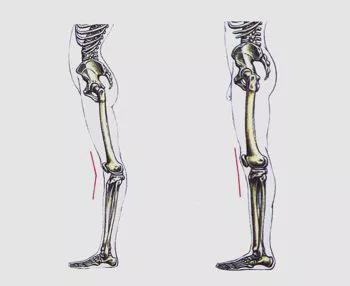

膝关节过伸又称膝关节过伸,英文为Hyperextend knee。人体膝关节正常的膝关节伸展范围是直到你能完全伸直你的膝盖,即你的大腿和小腿在一条直线上。如果在此基础上还能继续伸展膝盖,说明膝关节伸展过度了。 。站立时,如果膝关节达到过伸的位置,从侧面看,大腿和小腿会形成向后的弧线,所以有人把膝盖的过伸称为膝弓。

1、膝关节前麻痹或肌力低下型(因股四头肌麻痹或肌力低下开yun体育官网入口登录app,导致腘绳肌力量减弱开yun体育官网入口登录app,膝关节在伸展位时无法稳定,膝关节被迫在伸展位行走承受重量时)

2.膝后侧麻痹或肌力低下型(腘绳肌和小腿三头肌均麻痹或肌力低下,膝后侧包括关节囊、韧带等松弛,可引起膝关节过伸)

1、小腿三头肌张力过高,导致踝关节背屈受限

2.股四头肌高度紧张或挛缩,膝关节伸展和过度伸展

3、股四头肌无力。此时患者依靠膝角弓反张来维持膝关节伸展,保持直立姿势。

4.腘绳肌和小腿三头肌较弱,也依靠膝角弓反张来维持直立姿势。